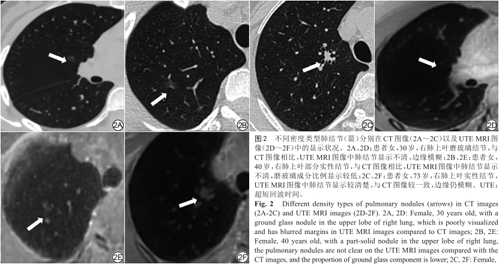

CT检查中肺结节类型可分为:磨玻璃结节,部分实性结节和实性结节[21]。UTE序列对不同类型结节的检出敏感度也是不同的。

HUANG等 [15]研究显示:UTE MRI对磨玻璃结节的检出率仅为70%,部分实性结节检出率达到91%,实性结节为92%。RENZ等[12]研究显示,在患有恶性肿瘤的儿童中,UTE MRI对实性肺结节的检出率为78.8%,亚实性肺结节(包括部分实性结节和磨玻璃结节)的检出率为68.0%。实性结节往往具有更高的检测率,但UTE MRI对亚实性结节的识别能力仍然可观[12,14, 15,22]。图2展示了不同密度类型结节在CT和UTE MRI图像中的表现。